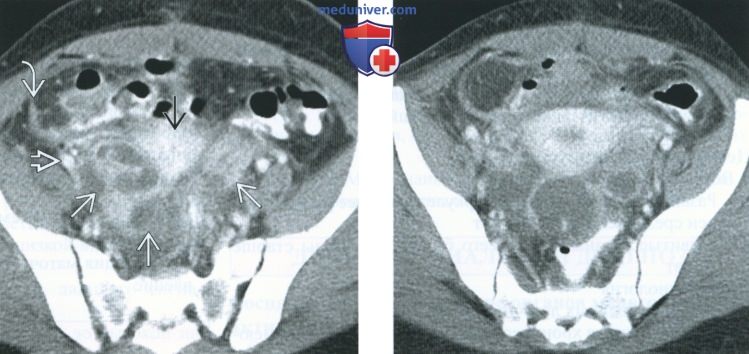

КТ-исследование абсцесса малого таза: Визуализация и диагностика

Раздел: Фотоальбом решений